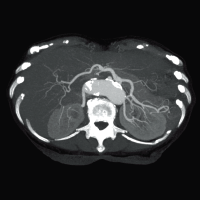

Клинические изображения

Для снижения лучевой нагрузки и повышения качества визуализации в КТ SUPRIA используются алгоритм интеллектуального перераспределения дозы IntelliEC и современный метод итерации IntelliIP, позволяющие провести сканирование с очень низкими значениями доз и получить изображения необходимого диагностического качества. В результате лучевая нагрузка на исследуемую область существенно снижается при сохранении высокого качества визуализации, особенно на уровне плотных паренхиматозных органов.